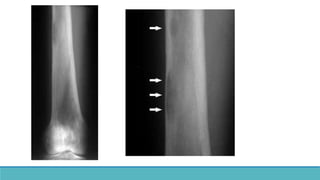

◦ OSTEOCLASTIC ACTIVITY IN HAVERSIAN CANALS.

◦ Radiographic translucencies in cortex – Cortical tunneling.

◦ Non specific – also seen in Paget’s disease of bone, normal childhood ( cond. with increased bone

turnover).

◦ OSTEOCLASTIC ACTIVITYIN HAVERSIAN CANALS. ◦ Radiographic translucencies in cortex – Cortical tunneling. ◦ Non specific – also seen in Paget’s disease of bone, normal childhood ( cond. with increased bone turnover).